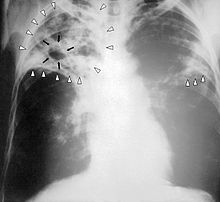

Өкпе туберкулезі алғашқы асқынбаған кезінде рентген арқылы қарағанда қарайған дақ (очаговый, инфильтративный) құсап көрінеді.

Қазіргі жағдайда ерте анықтау үшін негізгі құрал рентген болып есептеледі.[1]